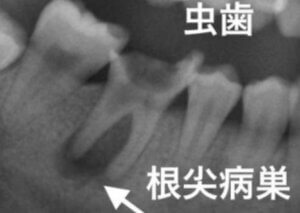

根尖病巣